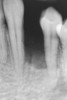

Figure 3  Preoperative radiograph of the failing implant in the site of tooth No. 22.

Figure 3

A 28-year-old Caucasian female presented to the periodontist with a complaint of a mobile implant in the site of tooth No. 22 (Figure 2 and Figure 3). The patient had a congenitally missing tooth No. 23. No. 22 had erupted into site No. 23, leaving a vacancy at site No. 22, and was the reason for the original implant at site No. 22.

The patient had no medical concerns and had a history of an implant placement in December 2002 when she was 25 years old. In February 2005, she presented with a mobile implant and an associated advanced peri-implantitis. Radiographic review at the initial examination demonstrated significant destruction of the dentoalveolar ridge around the implant as well as around the adjacent natural dentition. Emergency-based treatment involved surgical implant removal only and debridement of the infection (Figure 4 and Figure 5). Following uneventful healing, an advanced ridge defect was apparent at the edentulous site and moderate and advanced attachment loss noted at No. 22D and No. 21M, respectively (Figure 6 and Figure 7). This case demonstrates bone loss of two separate origins: lack of bone because of tooth agenesis and destruction of bone from inflammatory peri-implantitis.